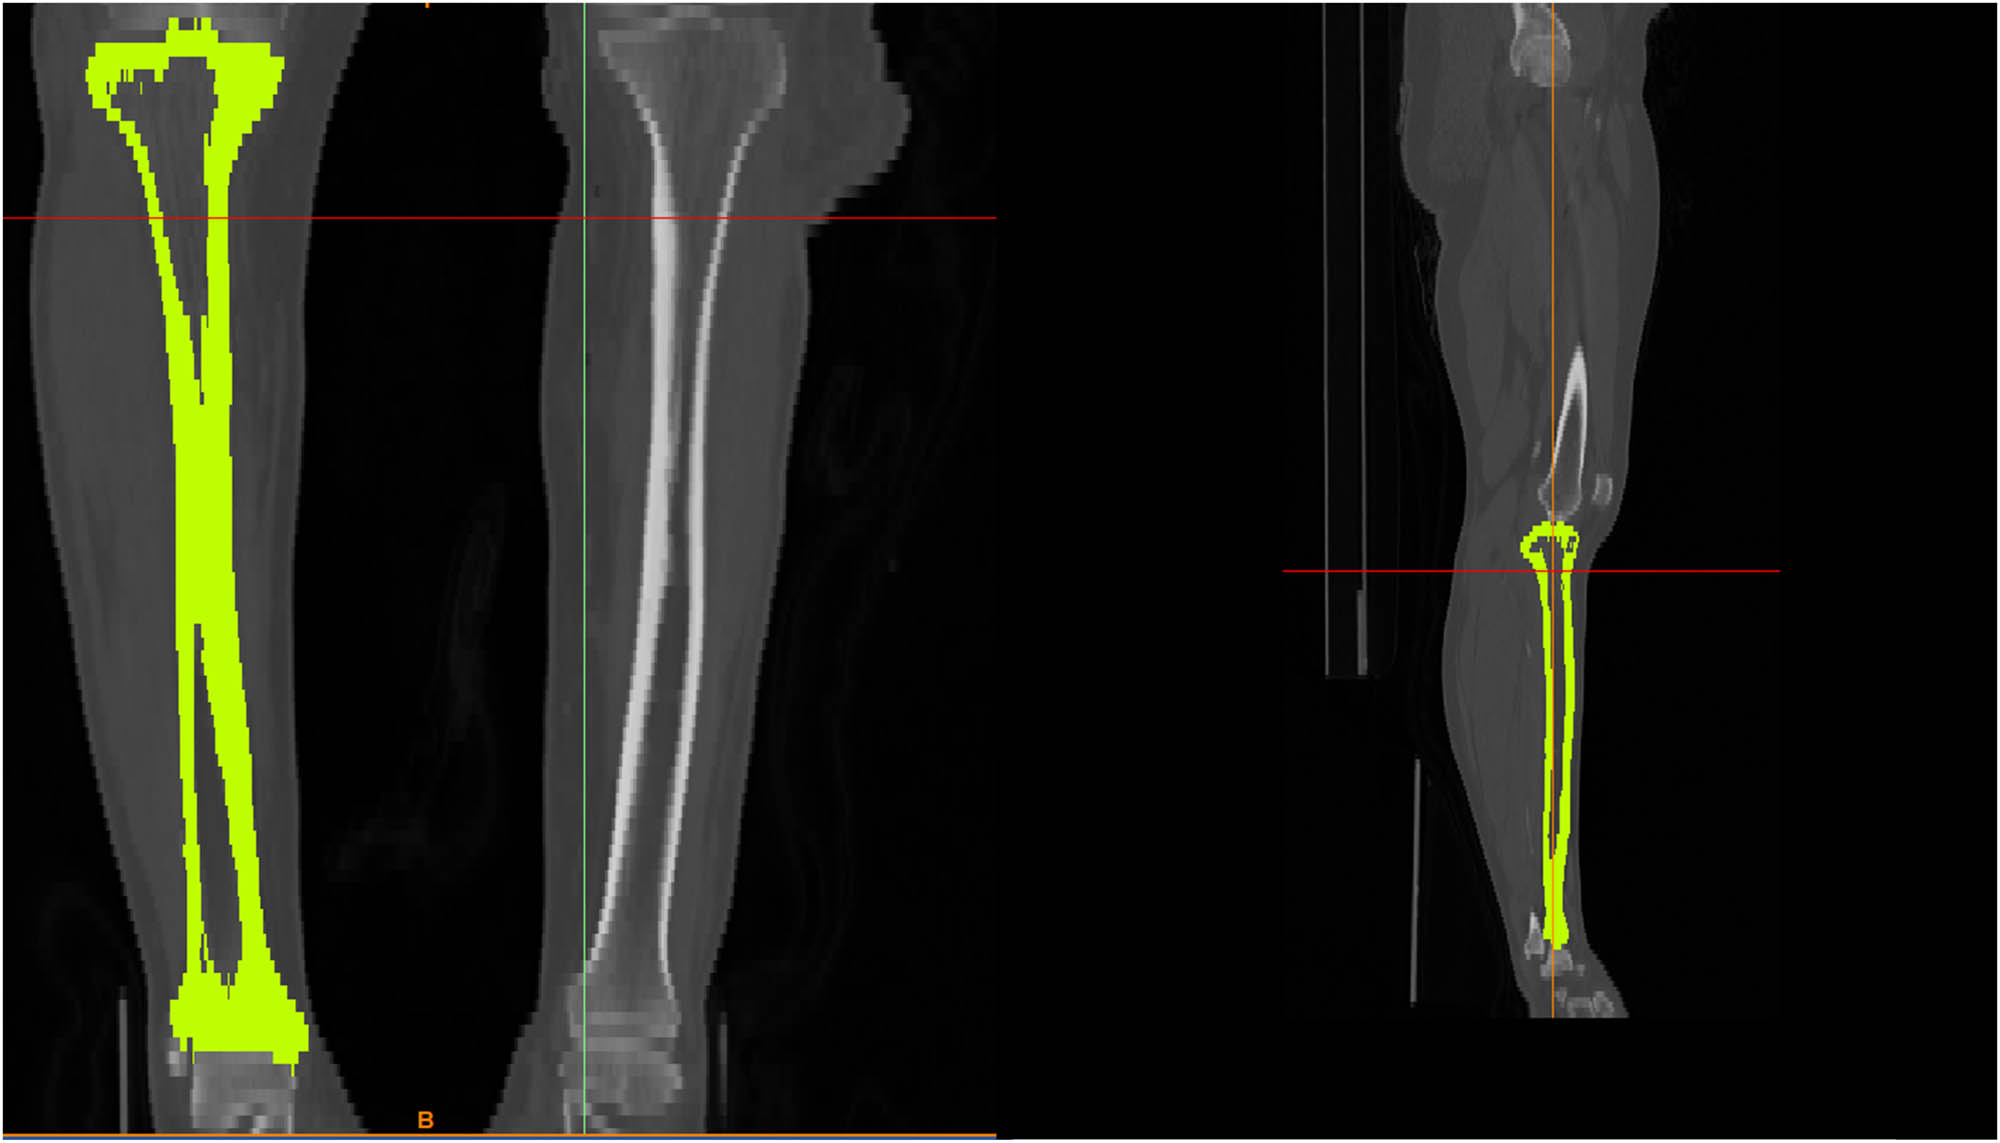

The present work used magnetic resonance imaging (MRI) data obtained from a patient as shown in Table 1. These data were utilized to generate a precise three-dimensional (3D) representation of various tissues via the utilization of sophisticated image processing software known as Mimics. The subsequent use of 3-Matic software was used to perform further image processing operations, including the segmentation of distinctly various kinds of tissues, resulting in the generation of an enhanced three-dimensional model, as shown in Figure 1.

Tibia bone undergoes a process of segmentation and treatment in order to facilitate the creation of a 3D module.

The model was refined by removing unnecessary data and reducing noise using 3-Matic, a software tool optimized for intricate geometric manipulations as shown in Figure 2(a). Additionally, a finite element mesh was generated to further enhance the model in Figure 2(b) and (c). Material properties were allocated to the 3D model by considering tissue types and bone density. The bone’s density was used to establish material properties, such as modulus of elasticity, and Poisson’s ratio of 0.3 in order to accurately replicate the mechanical characteristics of the bone, as shown in Figure 3.